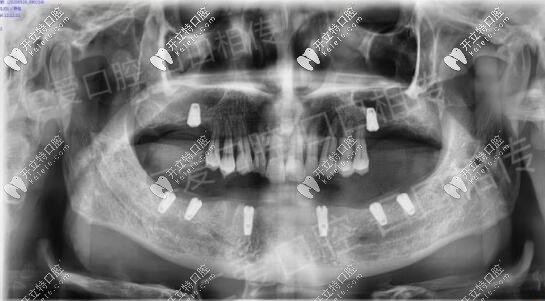

疫情前把該拔的殘根松動(dòng)牙拔除恢復(fù)到現(xiàn)在,主要設(shè)計(jì)的ALL-ON-N種6恢復(fù)下半口,今天已成功種植8顆植體

術(shù)后裝上過(guò)渡性樹(shù)脂義齒,等待種植體與骨質(zhì)結(jié)合較好之時(shí)再進(jìn)行長(zhǎng)久性牙齒佩戴,老爸現(xiàn)在咀嚼穩(wěn)定健康,重啟生活質(zhì)量,他高興,我也感覺(jué)欣慰。